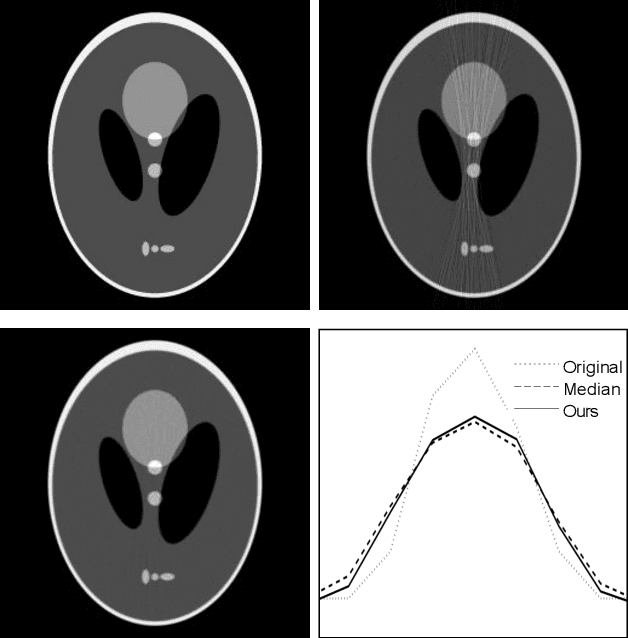

Abstract:Low-dose X-ray CT technology is one of important directions of current research and development of medical imaging equipment. A fast algorithm of blockwise sinogram filtering is presented for realtime low-dose CT imaging. A nonstationary Gaussian noise model of low-dose sinogram data is proposed in the low-mA (tube current) CT protocol. Then, according to the linear minimum mean square error principle, an adaptive blockwise algorithm is built to filter contaminated sinogram data caused by photon starvation. A moving sum technique is used to speed the algorithm into a linear time one, regardless of the block size and thedata range. The proposedfast filtering givesa better performance in noise reduction and detail preservation in the reconstructed images,which is verified in experiments on simulated and real data compared with some related filtering methods.